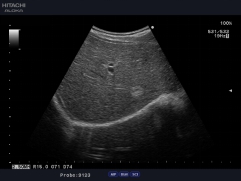

通過復(fù)合陣列探頭及SIP、AIP等多種成像技術(shù),為臨床帶來優(yōu)質(zhì)的二維圖像和敏感的血流,可以更加真實(shí)的反映血管的灌注情況,真實(shí)再現(xiàn)微細(xì)血管解剖形態(tài)。

作為原裝進(jìn)口的全身應(yīng)用型高檔全數(shù)字化彩色多普勒超聲診斷系統(tǒng),它在腹部、泌尿、婦產(chǎn)、乳腺、甲狀腺、淺表、腔內(nèi)、心臟等各個領(lǐng)域都有完美的圖像表現(xiàn)及豐富的應(yīng)用支持。